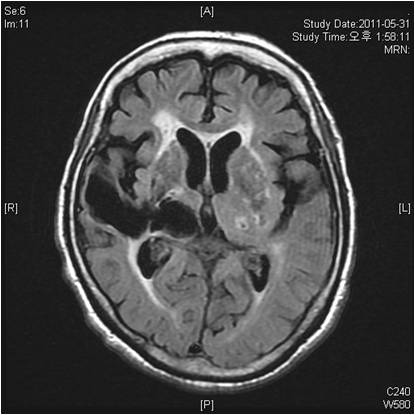

뇌경색 치료 방법

뇌경색 초기증상이 의심된다면 지금 바로 병원을 내방해 진단을 받고 적절한 치료를 손대는 것이 후유증을 감하는데 중요 해요. 시간이 관건이며, 뇌세포의 괴사, 증상 악화, 너무 늦으면 사망에 이를 수 있는 뇌혈관의 괴사를 피하기 위하여 증상이 나타난 뒤에 4시간 이내에 잘 맞은 약물, 시술 또는 수술을 신속히 실시해야 합니다. 치료로 즉시 하셔야 해요.